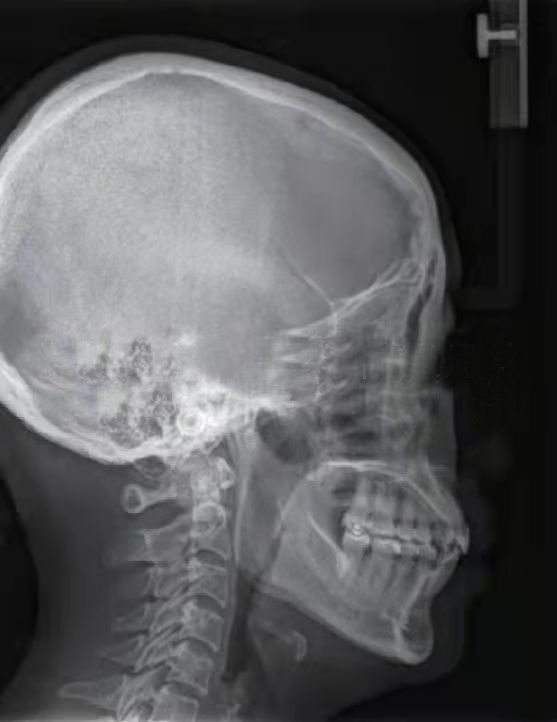

颞下颌关节由关节窝、髁突、关节盘及其周围软组织构成。髁突位于关节窝内,关节盘将髁突与关节窝分割为上下两个间隙,以避免骨性凹陷与髁突直接接触造成损伤。一般来说,髁突在关节窝中的矢状向位置关系更容易受到咬合闭合道及闭口位的影响,从而建立不良的关节结构关系,把关节盘挤出关节窝,造成髁突与关节窝之间的直接接触,损伤髁突。 髁突在关节窝中处于什么样的生理位置才有利于关节的功能运动及咬合,评价标准一直不统一。 近年来,更多的研究结果证实,在关节结构正常的条件下,牙尖交错位时的髁突在矢状向上基本处于居中的位置,即前后间隙甚至包括上间隙基本相等,这可以作为关节结构分析的参考。同时,牙尖交错位时,关节结构及其周围肌群甚至牙周状态均是协调舒适的,下颌运动时所有结构在这个过程中是轻便无障碍的。然而,这些理论均是建立在关节结构没有损伤的前提下,一旦结构发生损伤,比如髁突吸收,很难找到一个可量化的标准,理想的量化标准只能作为参考。 对于损伤后的关节,如何定位和评价其结构是否合理,目前没有相关概念和指标进行描述。理论上认为,颞下颌关节结构正常时,髁突在关节窝中的位置居中;已经损伤的髁突在关节窝中应有一定的修复空间,无论关节盘处于什么样的状态,只要在临床上患者没有任何不适且下颌功能正常,并经过一定时间的观察发现预后良好,就可以定义为关节舒适位。“舒适的”不一定全是形态健康完整的,损伤后的结构在舒服的环境中有可能慢慢修复;在不舒服的环境中,健康无从谈起。截至目前,还没有公认的关于关节结构,尤其是髁突位置和关节盘状态准确的、定论性的统一标准,也没有关于关节功能紊乱患者的治疗评价标准。

对咬合异常患者要进行临床检查、面型分析、影像学检查等,然后对结果进行综合分析。临床面诊是第一位的,不仅可以看到患者静态的一般情况、面部和咬合特征,还可以观察到患者包括肌位、牙位状况在内的咬合运动、语言、呼吸、发音等功能特征。动态观察一定不可忽略。 除此之外,基于功能运动的咬合分析,对关节病患者使用什么仪器和检查方法,要根据具体情况选择。比如,对下颌各种运动形式的各种检查,可以观察到下颌的运动状态及牙齿尖窝接触点的情况,用来分析咬合是否有碍关节结构和功能的敏感点。具体的方法包括观察法、手诊法、咬合纸检查、T-Scan(T-扫描)动态咬合力检查、髁突运动轨迹描记、头影测量、夜磨牙片、牙尖斜度测量、锥形束CT检查、MRI(磁共振)检查等。 需要注意的是,所有的测量方法都有侧重,医生可以根据实际需要选择一种或几种方法。 一般来说,应用单一的方法难以准确地发现问题;几种方法联合应用,相互印证,相互补充,能让医生更加全面地分析是否存在不足或不正确。但是,对于致力于咬合病治疗的专业人士,掌握头影测量、锥形束CT和MRI的检查方法、制取与分析很有必要,这些也是比较基本的技能;否则,很难做出一个完整、系统、科学的治疗方案。